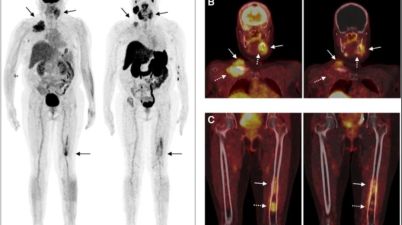

Çalışmanın amacı, multipl miyelom (MM) hastalarında kullanılan [18F]FDG ve [68Ga]Ga-PSMA-11 PET/CT görüntüleme yöntemlerini karşılaştırmaktı. Bu yöntemlerin MM lezyonlarını tespit etme başarısı ve bulunan lezyonların özellikleri incelendi. Çalışmaya 20 hastanın katılımı […]